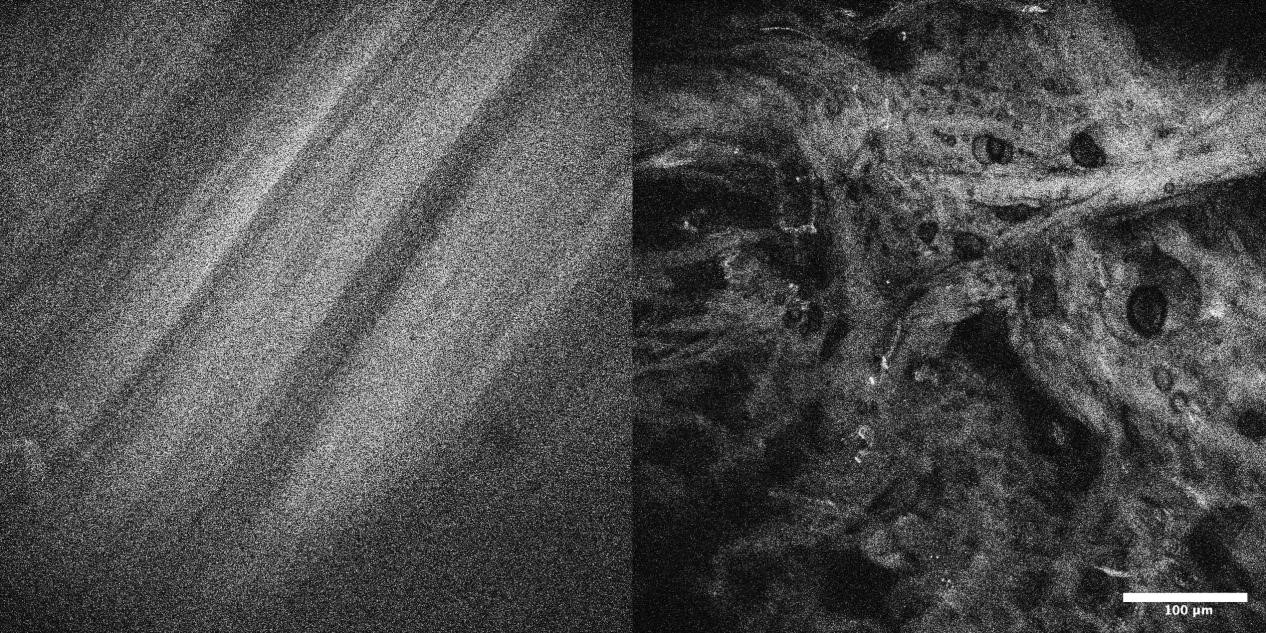

4、自体荧光OptiScan成像

左:ACL中有序的胶原纤维;右:ACL中过度负荷后的无序胶原纤维。

注:前交叉韧带(ACL)的自体荧光成像。本研究着眼于疲劳相关微损伤导致的前交叉韧带失效。Scale bar=100μm。